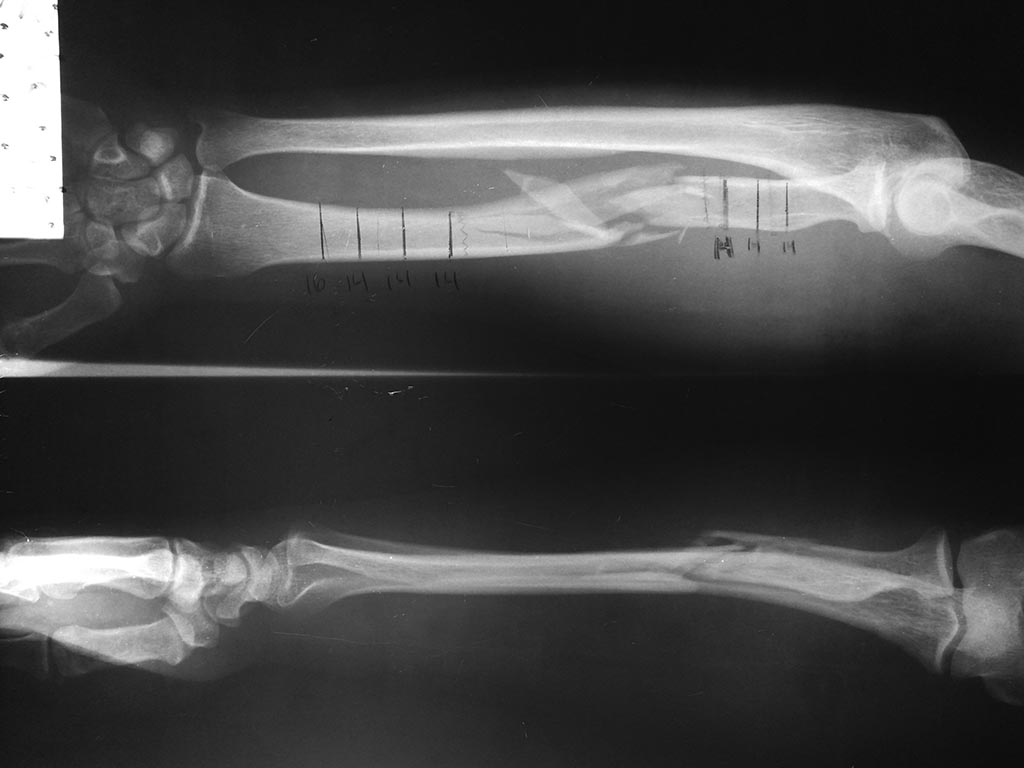

Help me with this patient, multifragmentary radial shaft fracture.

This patient has a fall of historia height whit outstretched hand and Wrist, the x rays shows a multifragmentary fracture of radial shaft, the Marín problema is that this patient havent money for a locking compresión plate, that is the óptimal Surgical treatment for him, so he buy a dcp plate, can anyone help to choose the best aproach and treatment with this material. Atatchment the x rays picture.